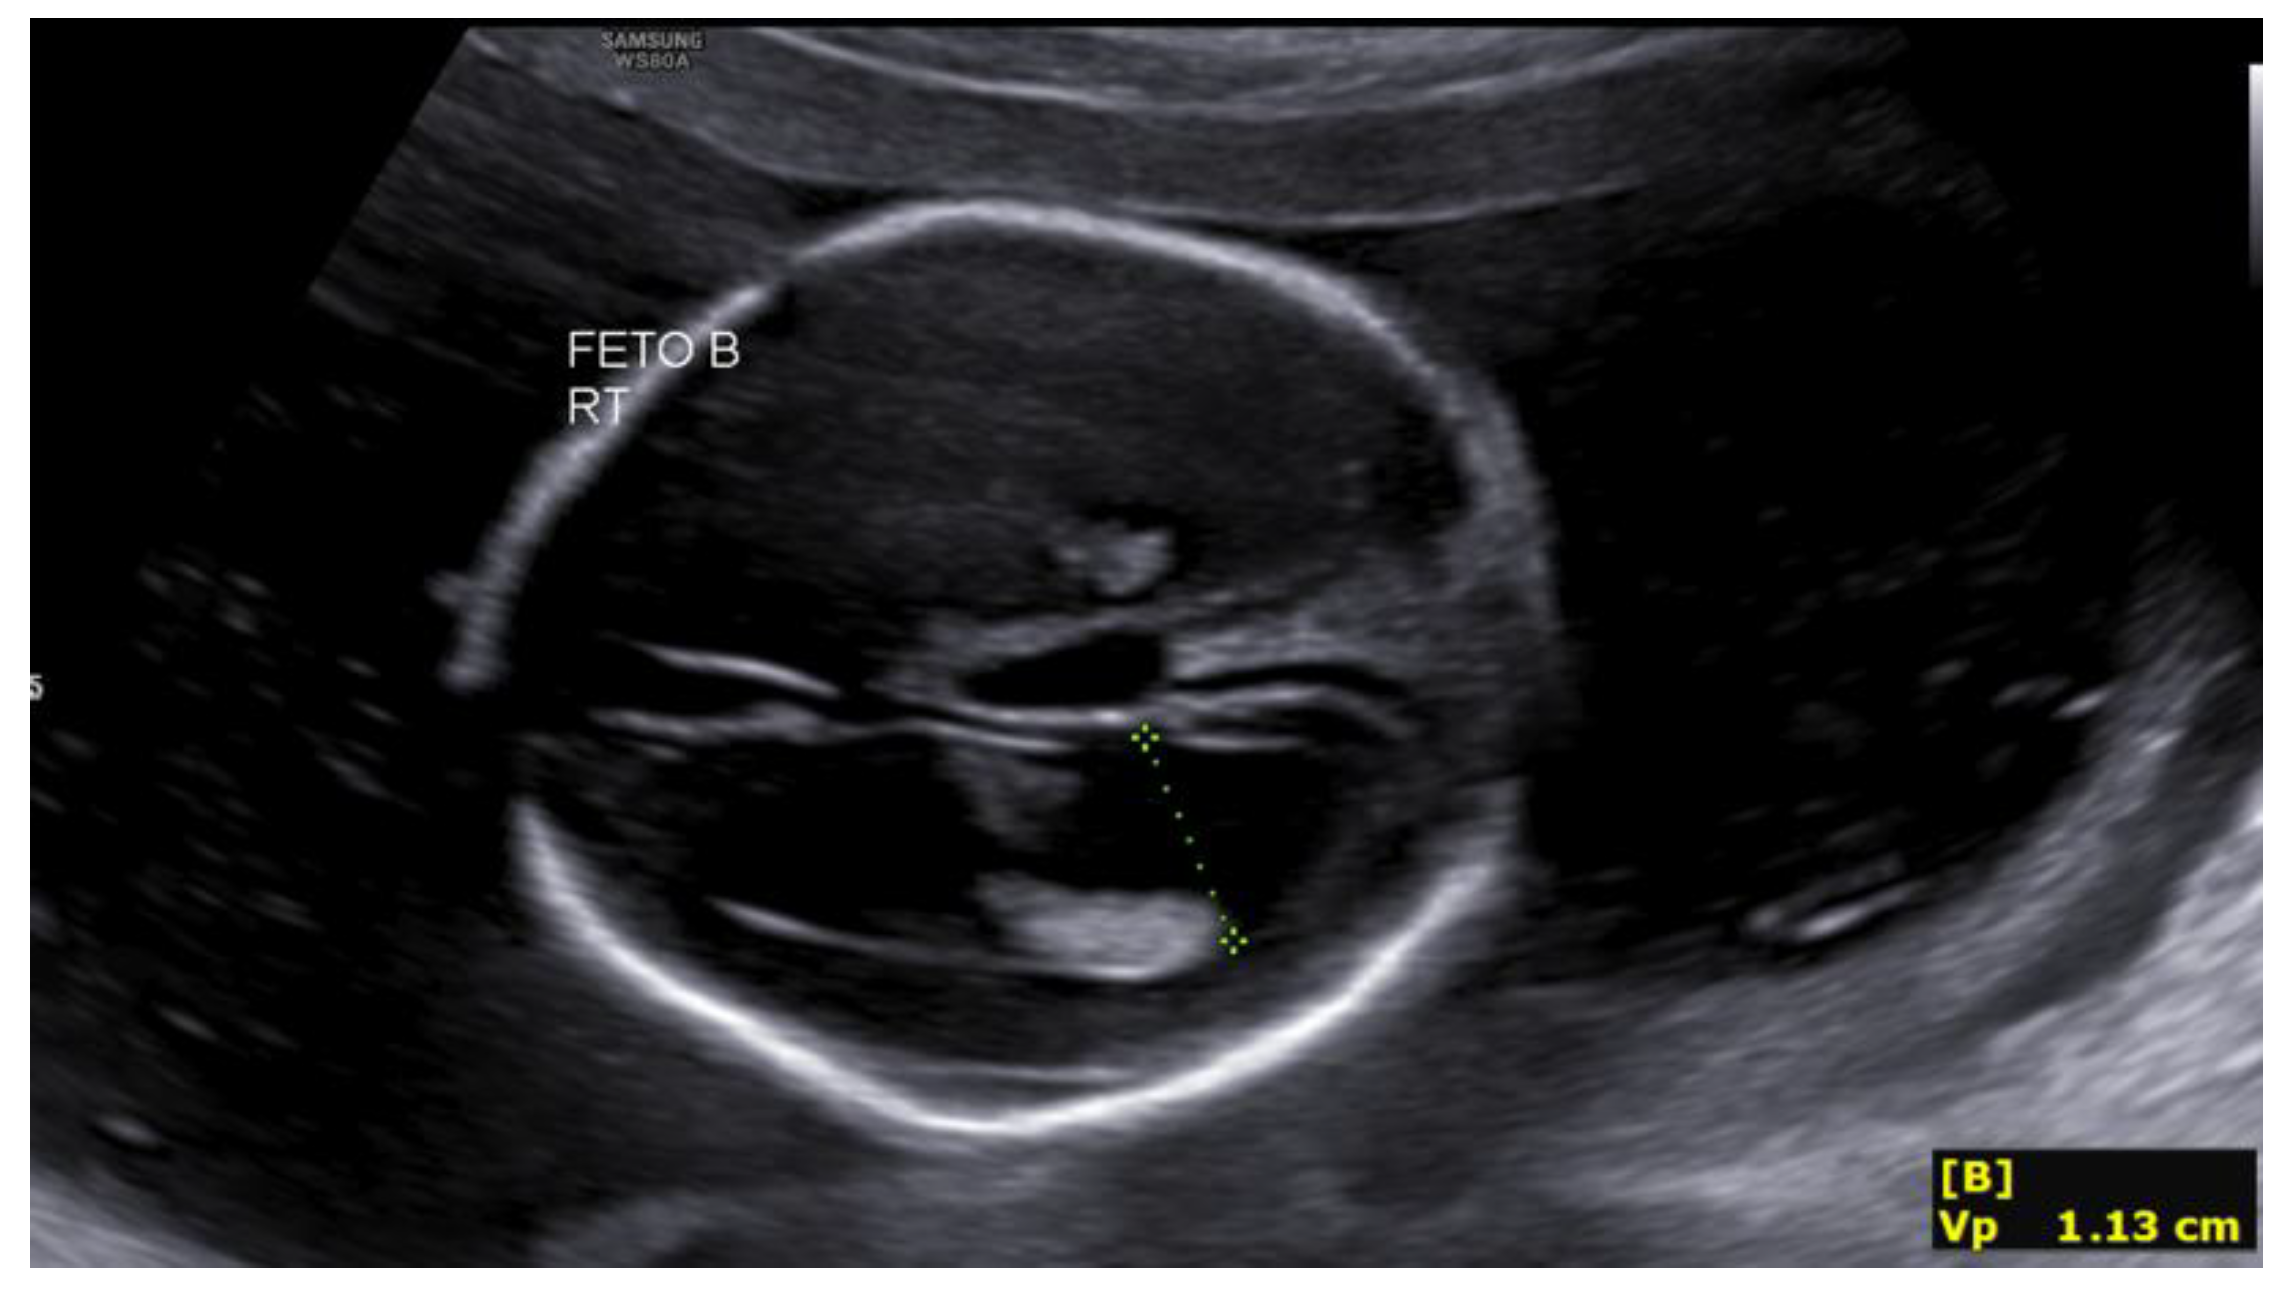

The second fetus, located in the right hemiabdomen in transverse lie, showed biometry consistent with 17+4 weeks, with an estimated fetal weight of 209 g, a single umbilical artery, and normal umbilical Doppler. Intracranial assessment demonstrated bilateral ventriculomegaly (Figure 1), predominantly posterior (anterior horns 6 mm; posterior horns 11–13 mm), and a dilated third ventricle measuring 7×3 mm (Figure 2), with a normal-appearing posterior fossa and corpus callosum. The intertwin discordance in estimated fetal weight was 11%.

Figure 1. Ventriculomegaly in the second fetus at 19+4 weeks.